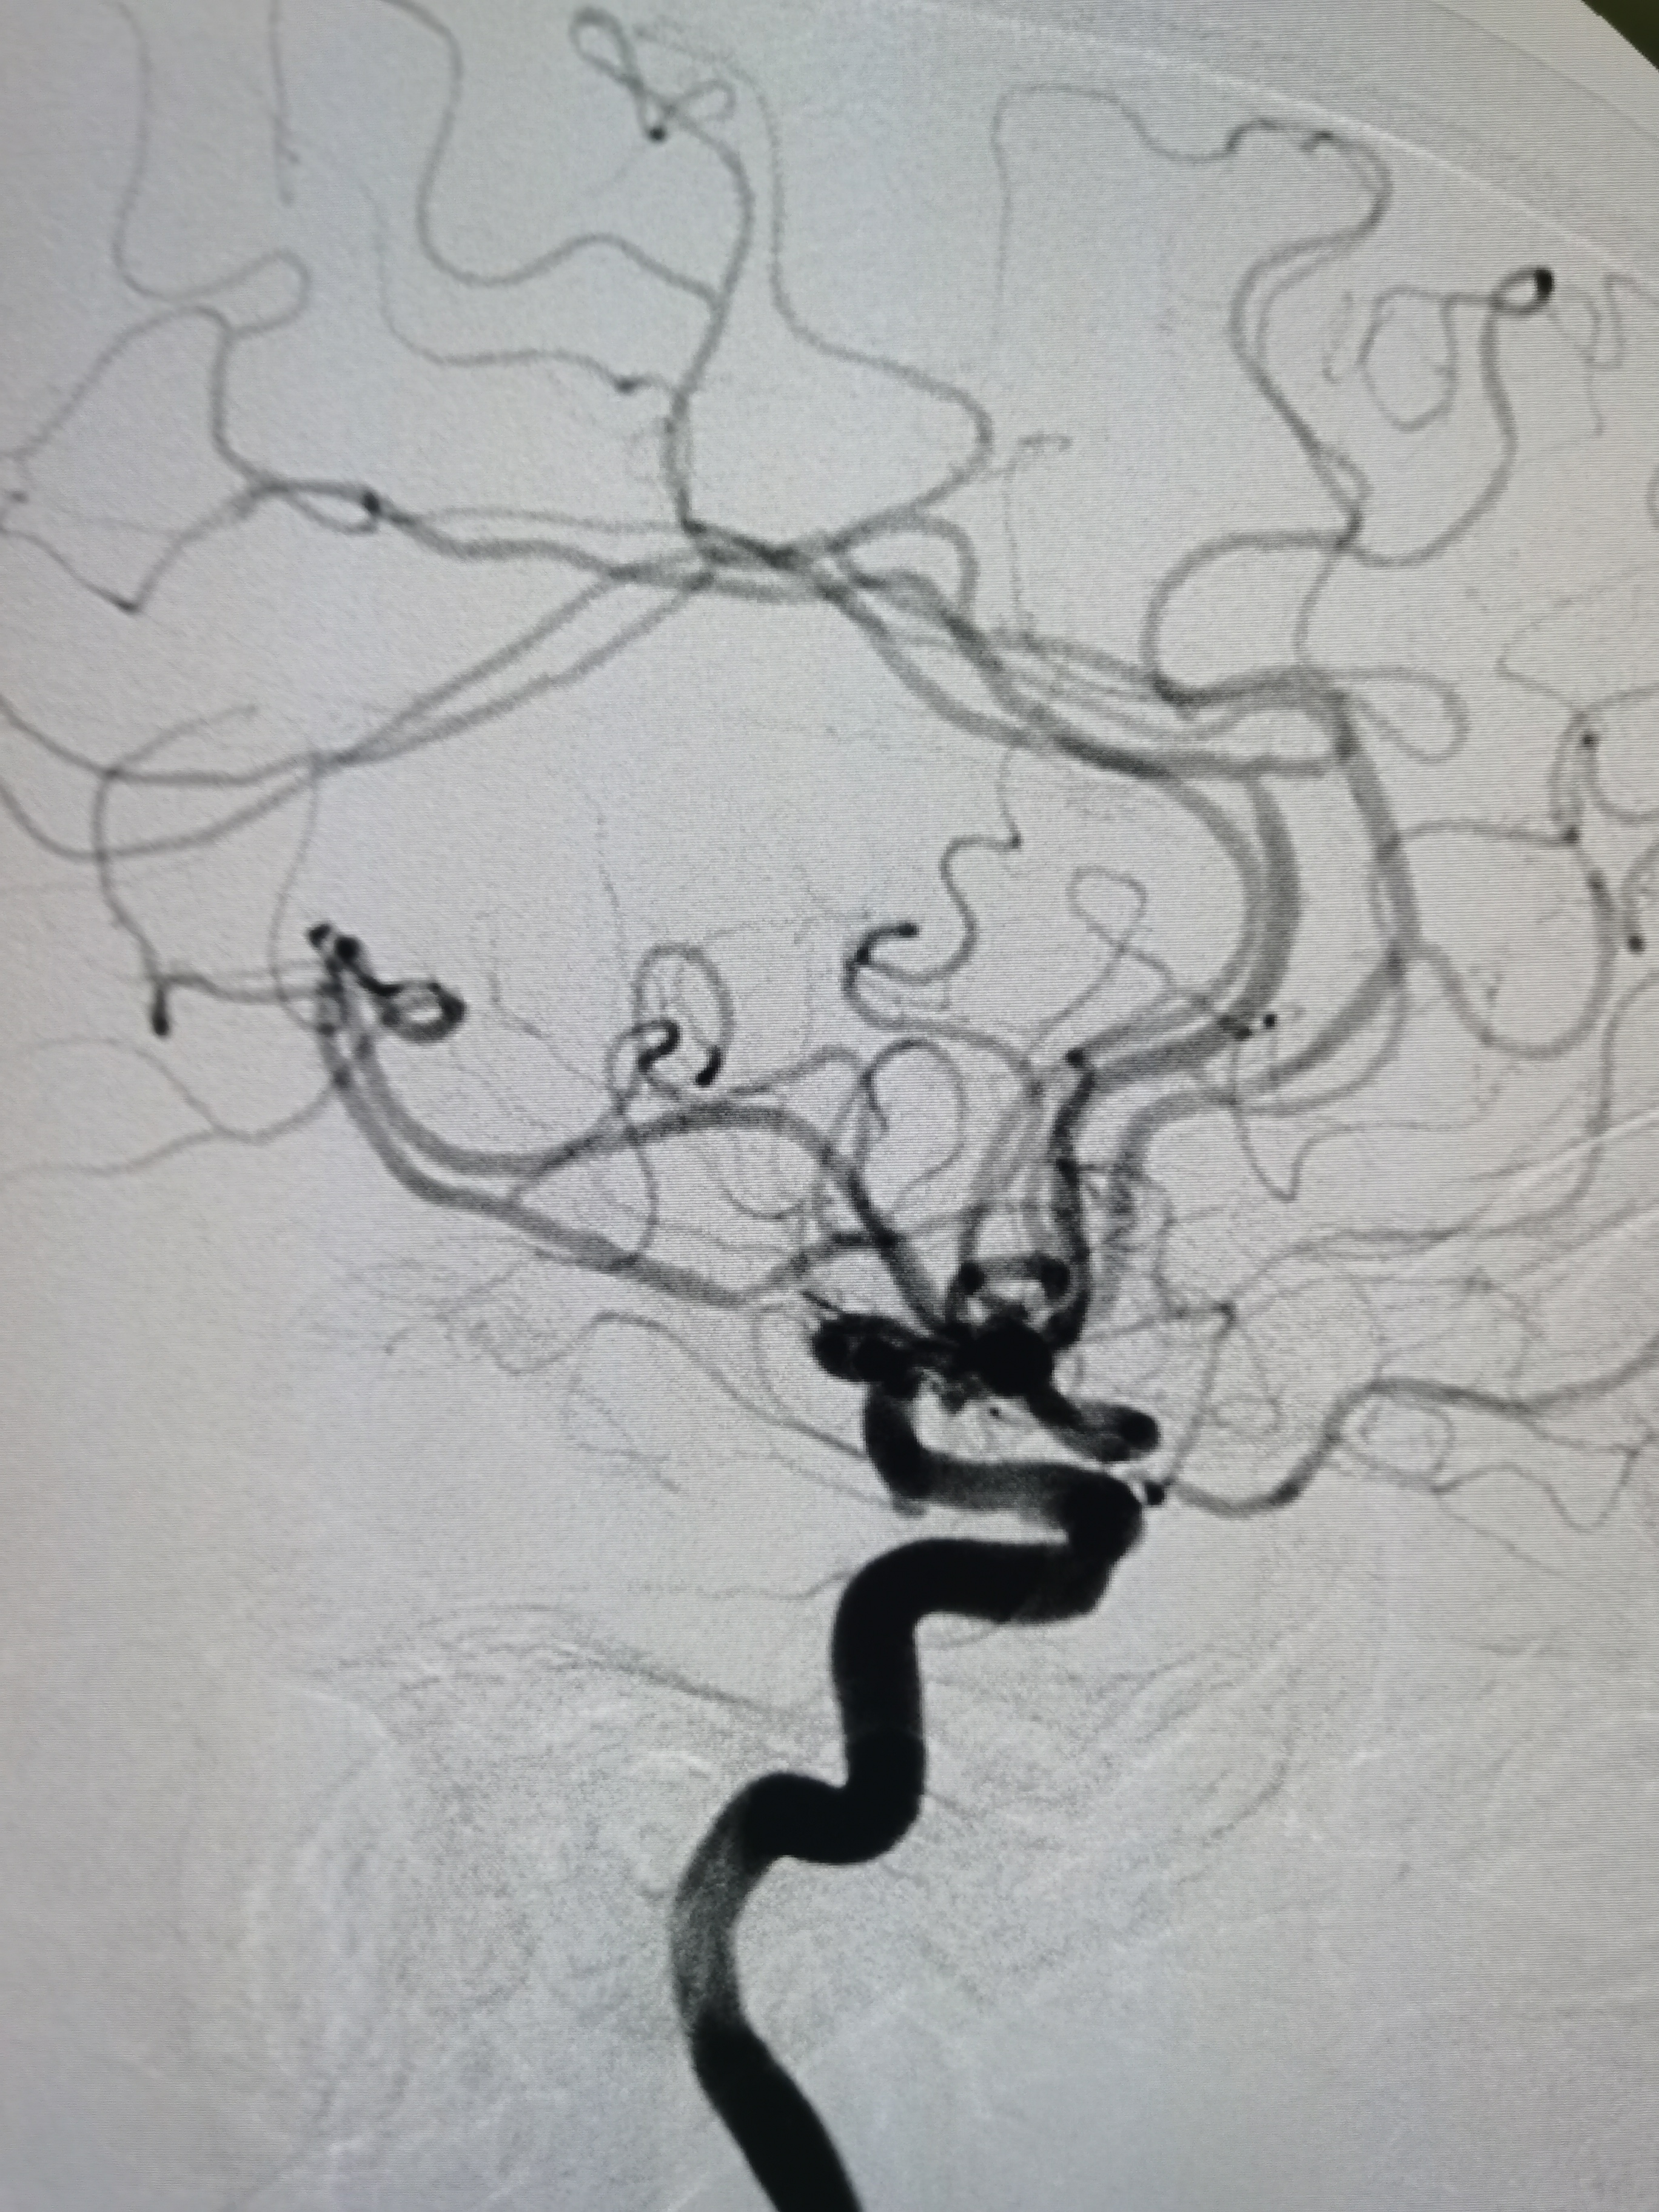

右侧颈内动脉起始部粥样硬化斑块形成。

颅内侧位显影可。

右侧大脑中动脉M1段重度狭窄。

右侧大脑中动脉M1段重度狭窄,病变处存在豆纹动脉。

左侧颈内动脉起始部正常。

左侧大脑前动脉发育不良。

左侧大脑中动脉显影正常。

右椎动脉劣势。

颅内血流可。

左椎动脉优势。

基底动脉显影正常。